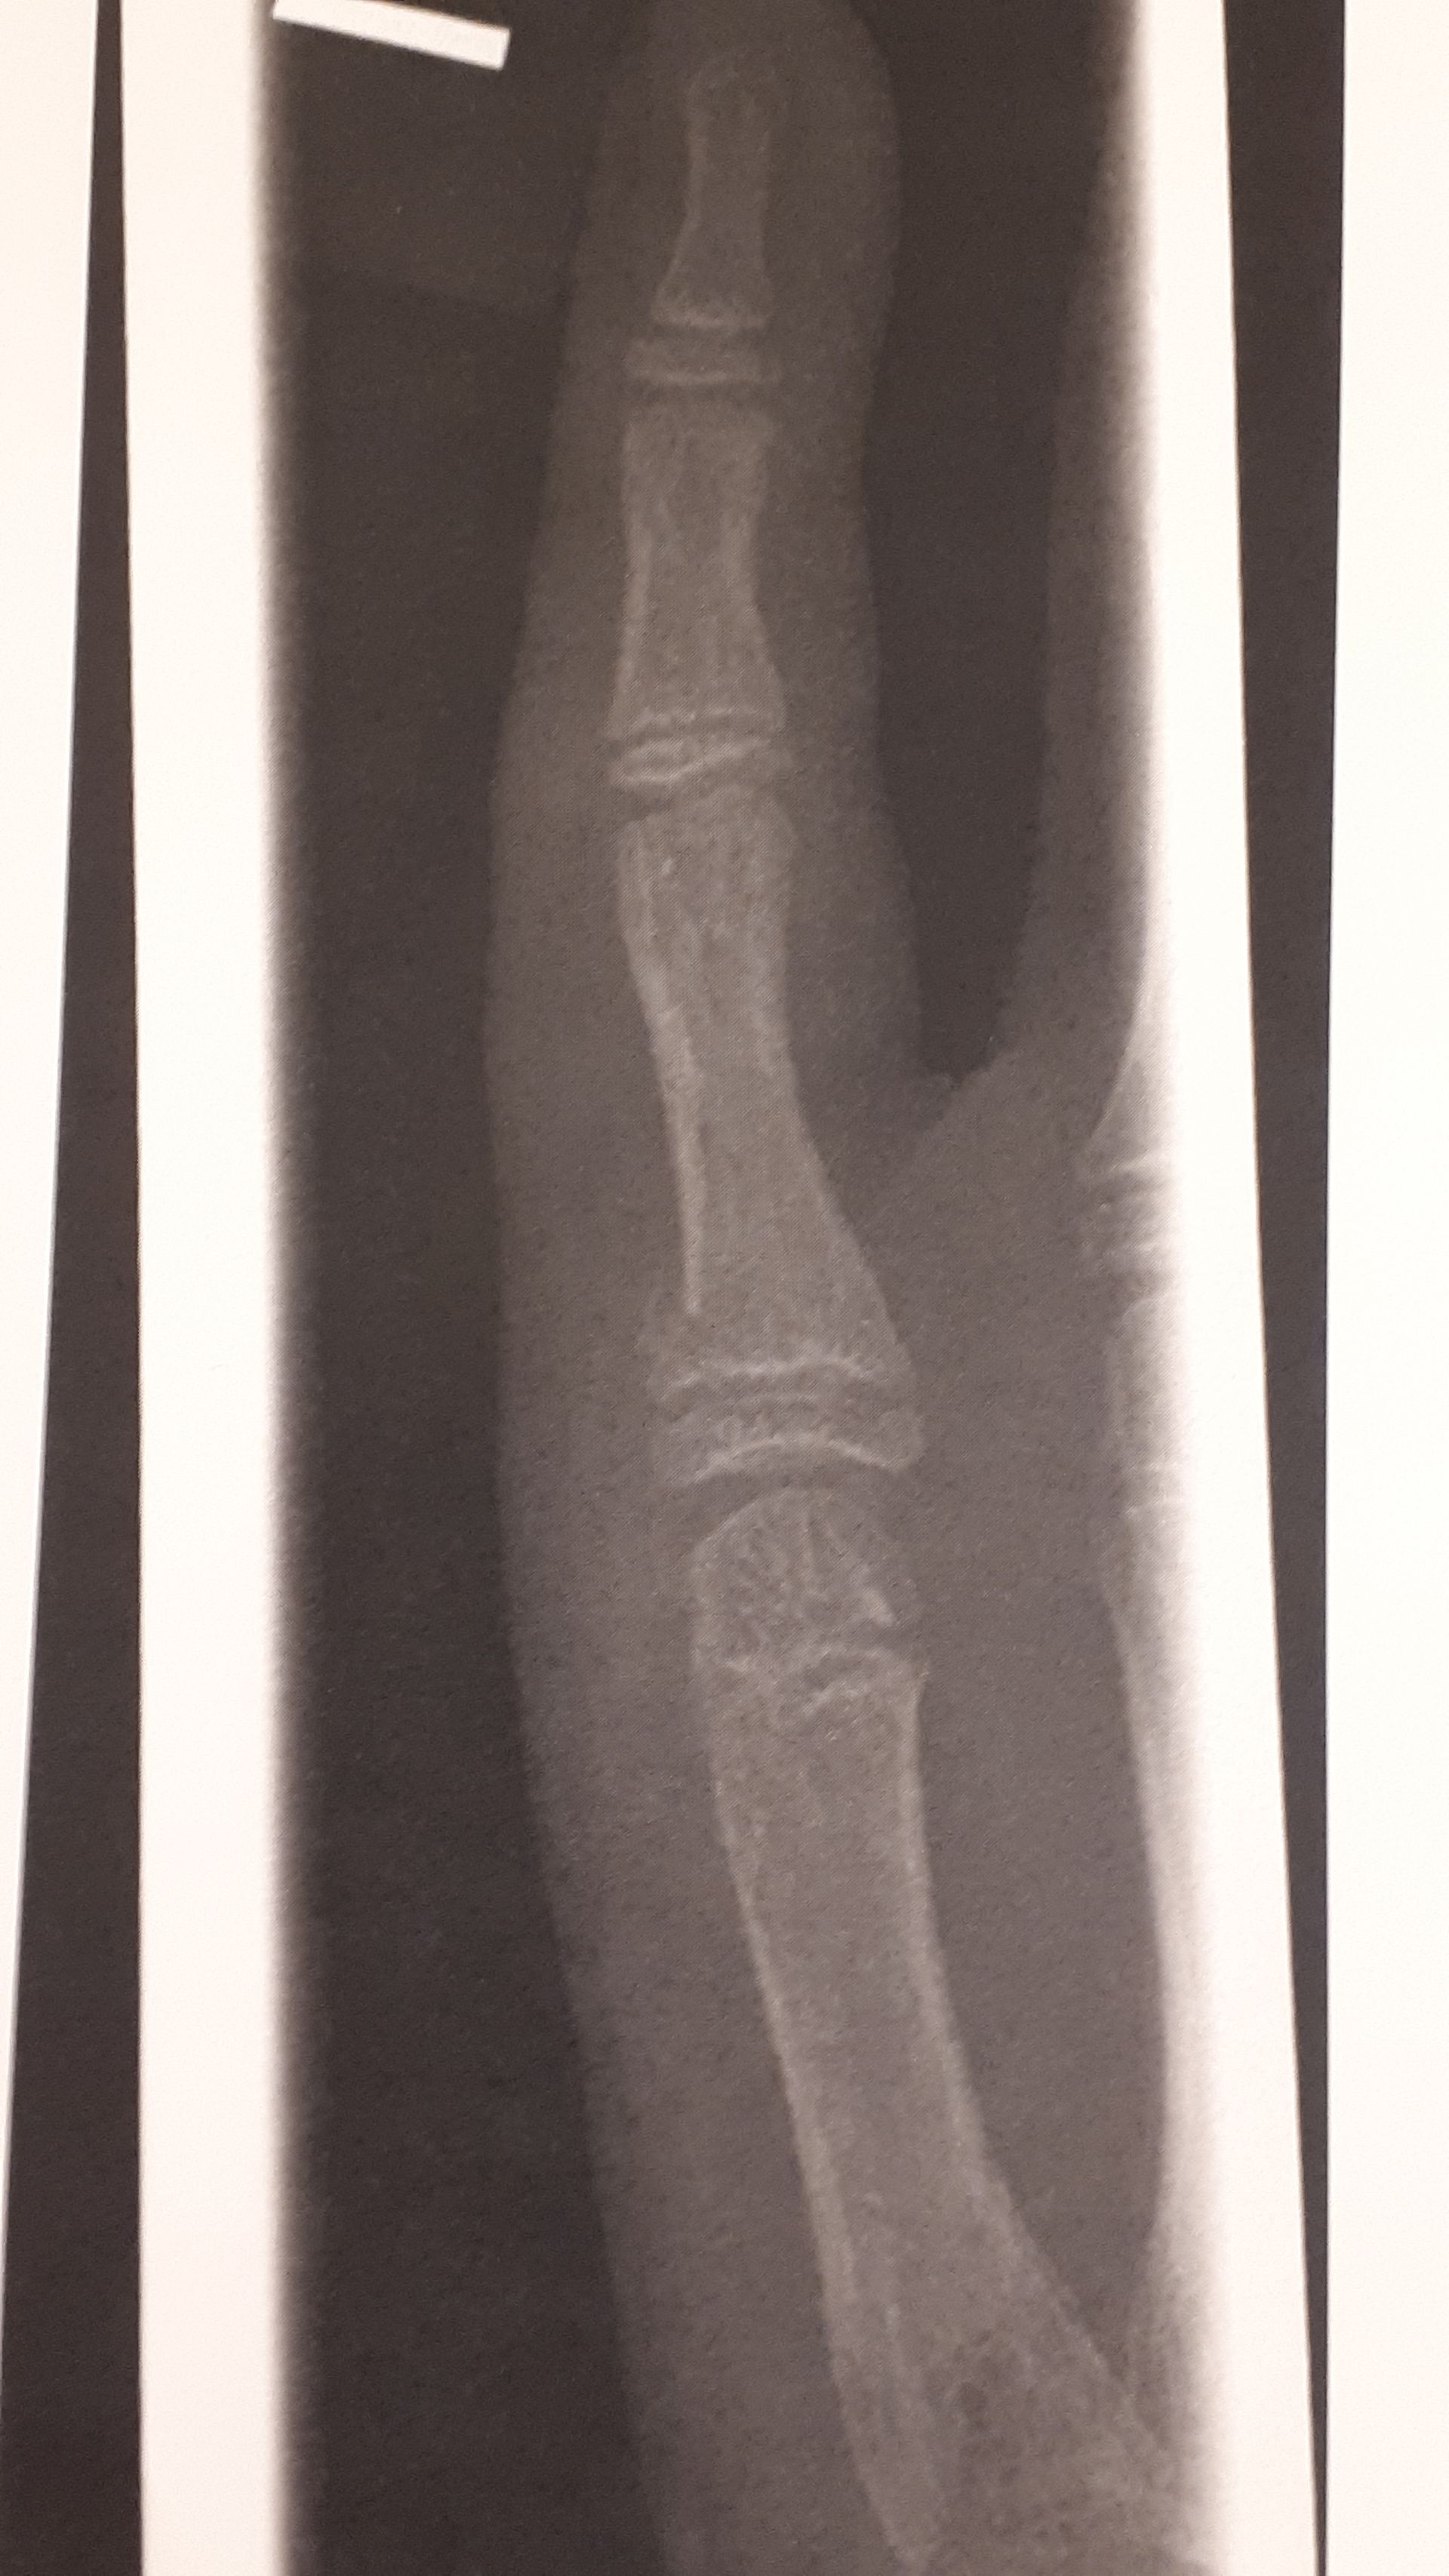

CactusCat14108 #gegenDatenschutz-Mannvor 3 MonatenKatze®️Am kleinen Finger OP haben die bei mir nd gemacht, lohnt nd sagten sieBei mir isser verdreht, und muss mit so 2 kleinen drähten befestigt werden

Anonymvor 3 MonatenCactusCat14108 #gegenDatenschutz-MannBildkomisch dass man es auf dem bild nicht erkennt, aber der arzt hat es erkannt

Anonymvor 3 MonatenAnonymkomisch dass man es auf dem bild nicht erkennt, aber der arzt hat es erkanntalso dass es gebrochen ist

Ist verdreht

Bei mir isser verdreht, und muss mit so 2 kleinen drähten befestigt werden

Und die drähte kommen unter die haut halt

Geschmetterter volleyball volle kanne dagegen bekommen

komisch dass man es auf dem bild nicht erkennt, aber der arzt hat es erkannt

also dass es gebrochen ist